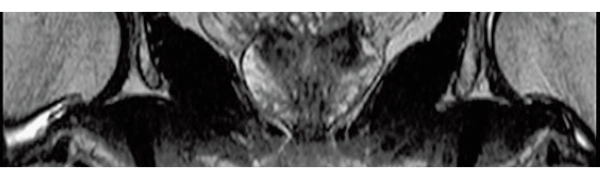

MPR COR

3DisoFSE T2WI

0.75×0.75×1.1(0.55)mm